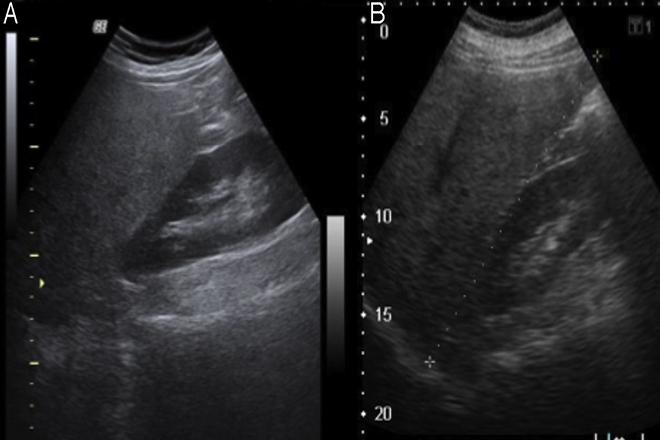

DESCRIPCIÓN ECOGRÁFICA DEL HÍGADO.

• Tamaño.

• Morfología: características “normales” de sus bordes: bien definidos, lisos y regulares, o normales de sus bordes: irregulares, granulados etc.)

• Ecogenicidad (brillo)

• Estructura (homogeneidad)

Cortes longitudinales en exploración ecográfica hepática.

1. – corte longitudinal sobre lóbulo derecho (riñón derecho, lóbulo derecho      como estructura dominante.